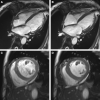

Case summary: A 68-year-old female patient with a pleural epithelioid angiosarcoma developed heart failure with reduced ejection fraction and elevated serum biomarkers following doxorubicin treatment. After implementation of a recommended cardioprotective medical therapy including torasemide, ramipril, carvedilol, and spironolactone, the patient suffered two cardiac decompensations within 4 weeks after initiation of a paclitaxel regimen and pleural radiation therapy due to pain exacerbation. Despite a continuous application of the cardioprotective medical treatment regimen, no improvement of left-ventricular ejection fraction (LVEF) was detected in a 4-month follow up. Interestingly, after omitting ramipril and implementing low-dose sacubitril/valsartan (26/24 mg), we observed a decrease in serum biomarkers within 3 months as well as a significant improvement of LVEF within 6 months. After nearly 10 months of disease stabilization under paclitaxel, the patient suffered progressive cancer disease and deceased 1 week later after the initiation of a therapeutic attempt with pazopanib.